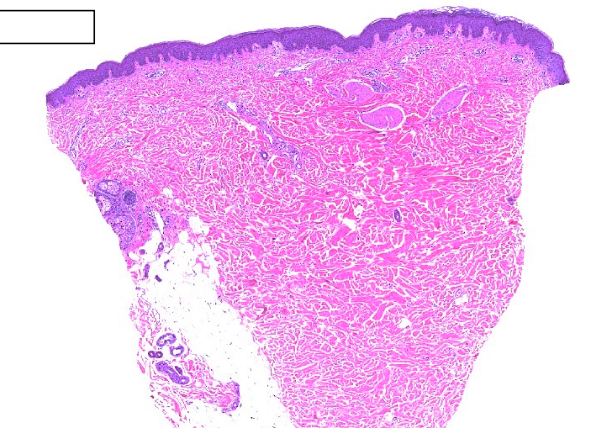

Vad är detta?

Normal hud